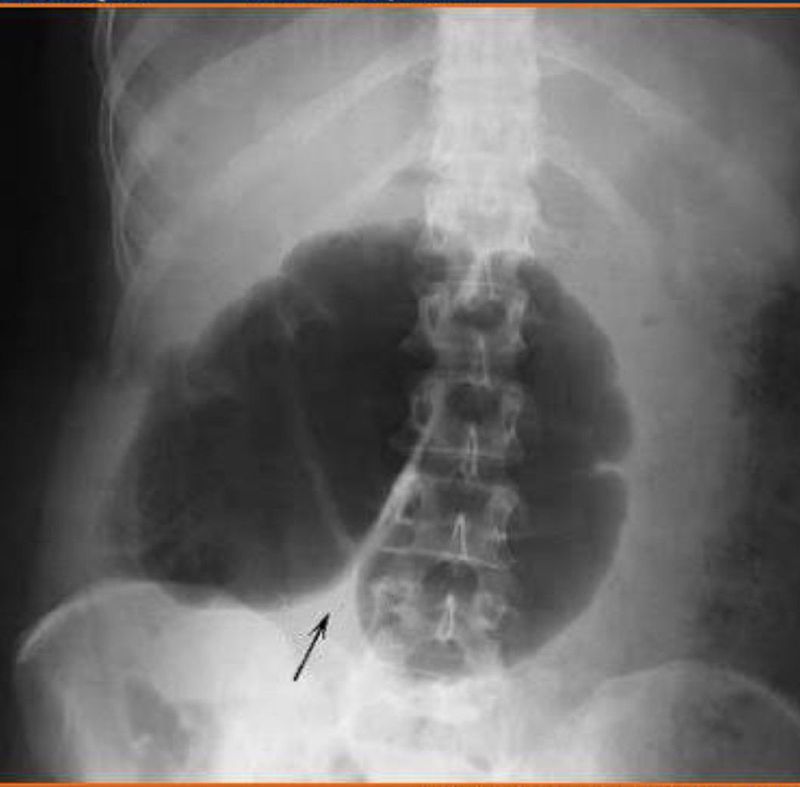

Cecal volvulus

Abdomen

Radiography

Volvulus